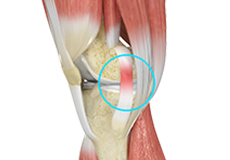

Hoffa's Fat Pad Syndrome

Hoffa’s fat pad syndrome also called fat pad impingement, infrapatellar fat pad syndrome, and Hoffa's disease, is a condition characterized by anterior knee pain, pain in the center, and front of your knees, due to inflammation of the Hoffa’s fat pad.